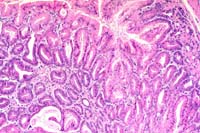

2x

obj

- Case 15-3. Glandular Stomach. Hyperplastic zone is

3-4x as thick as adjacent normal mucosa. Some crypts are cystic.

There ae both submucosal and subserosal lymphoid follicles.

10x

- Case 15-3. Glandular stomach. Mucosal glands are occasionally

cystic and diffusely hyperplastic, but uniform and well oriented

to their basement membrane.

- AFIP Diagnosis: Stomach, glandular: Hyperplasia, adenomatous,

focally extensive, with mild multifocal lymphoplasmacytic gastritis,

129 x C57BL CYP1A2 -/- (knockout) mouse, rodent.

- Conference Note: A focally extensive area of the gastric

glandular mucosa at the junction with the squamous stomach is

thickened five to ten times normal. This plaque-like thickening

is characterized by long, arborizing papillary fronds of hyperplastic

mucosa usually lined by a single layer of tall columnar epithelial

cells. Scattered throughout the mucosa are variably-sized, dilated

or cystic glands partially filled eosinophilic proteinaceous

material occasionally admixed with mineralized debris. A mixture

of parietal cell, chief cell, and mucous neck cell hyperplasia

is present, and occasionally the epithelial cells pile-up several

layers thick. Some sections contain gastric glands that have

herniated through the tunica muscularis into the tunica serosa.

Scattered within the submucosa and serosal adipose tissue there

are nodular aggregates of lymphocytes and macrophages.